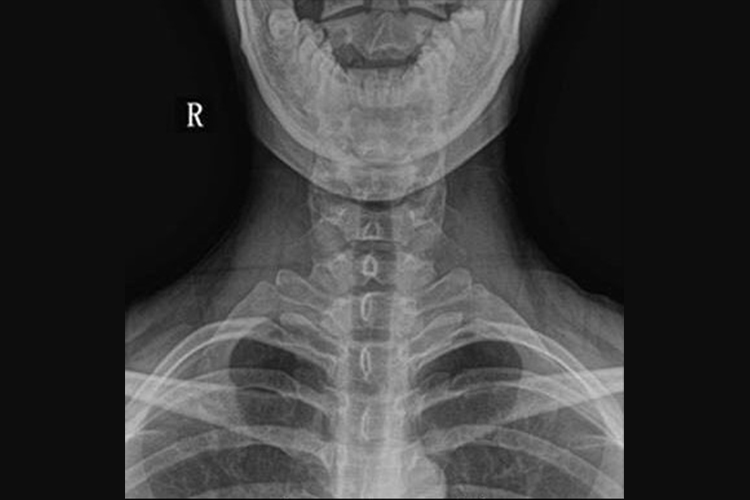

正侧位片图片

颈椎正位片和侧位片的表现不同,具体如下:

颈椎正位片:椎体呈长方形,从上向下依次增大,周围为一层致密的骨皮质,密度均匀,轮廓光滑。椎体两侧有横突影,在横突内侧可见椭圆形环状致密影,为椎弓根的投影。在椎弓环的上下方为上下关节突的影像,椎弓板由椎弓根向后内延续,在中线融合成棘突,投影于椎体中央的偏下方,呈尖向上类三角形结构。